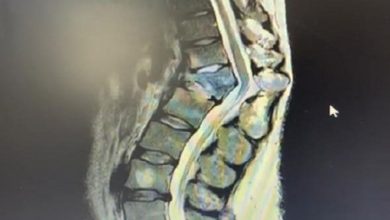

“جراحة العمود الفقري” بـ”السعودي الألماني” يعيد المشي الطبيعي لمريض “تحدُّب شديد”

أعلن قسم جراحة العمود الفقري بالمستشفى السعودي الألماني مؤخرًا نجاح عملية معقدة، أُجريت لمريض كان يعاني تحدبًا شديدًا بالعمود الفقري،…

للعلاج طريقان.. “الصالح”: 20% من السكان يعانون انزلاقات فقارية و”جنف”

أكد العادات الصحية وقال: نؤدي جميع الحالات في “دله” بأحدث التقنيات للعلاج طريقان.. “الصالح”: 20% من السكان يعانون انزلاقات فقارية…